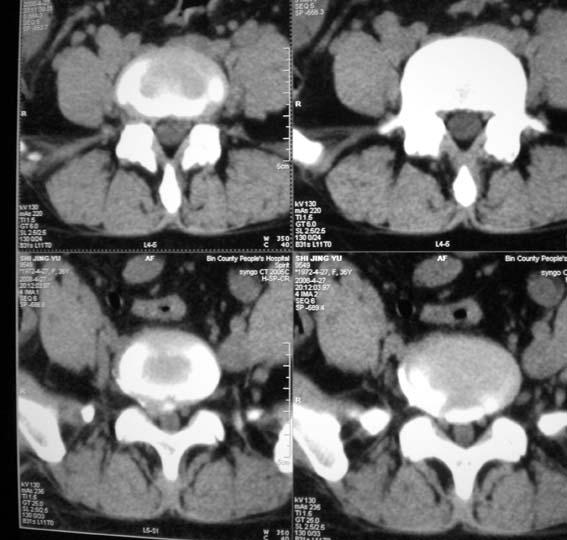

女,36岁,腰痛多年,坐久后,起身疼痛难忍。

考虑:1、腰5-骶1椎间盘突出(右旁中央型)。

2、腰5椎体下终板平面后缘后纵韧带钙化。

腰4/5椎间盘轻度膨出,腰5/骶1椎间盘突出(右旁中央型)伴局部椎间盘钙化。